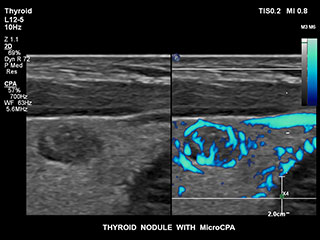

Ultrasound MicroCPA Small Vessel Visualization

MicroCPA

これまで、血流が少ない血管構造の血流情報は容易に収集できませんでした。しかし、EPIQの新しいMicroCPA機能を使用することで、低流速の微小循環を素早くかつ簡潔に描出できるようになり、臓器への灌流や小血管床の評価における診断確度が向上しました。